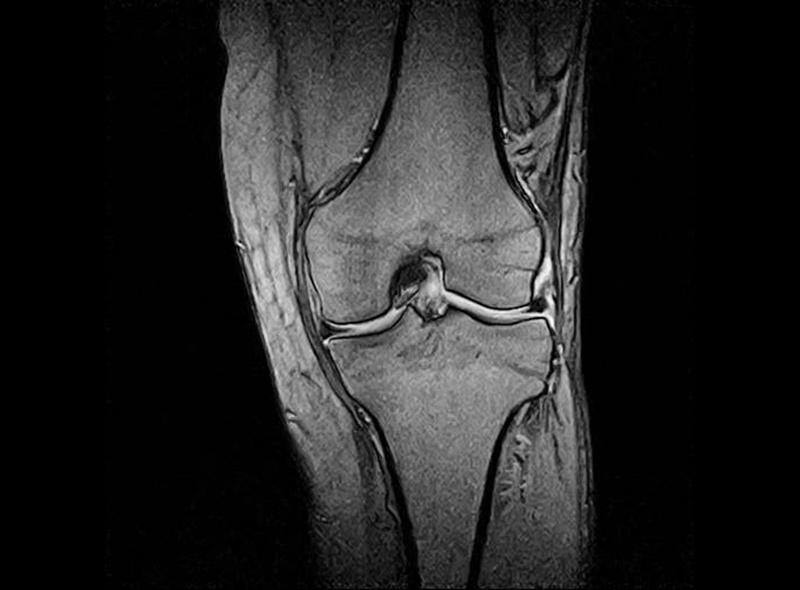

MRIを使った検査・診療

レントゲンでは評価することが出来ない靭帯や骨の状態を詳しく評価することができます。

靭帯損傷や腰椎圧迫骨折や腫瘍の正確な診断が可能です。

当院のMRIはオープン型ですので、狭い空間が苦手な方も少ないストレスで検査を受けることが出来ます。

MRI検査画像

膝(半月板損傷)